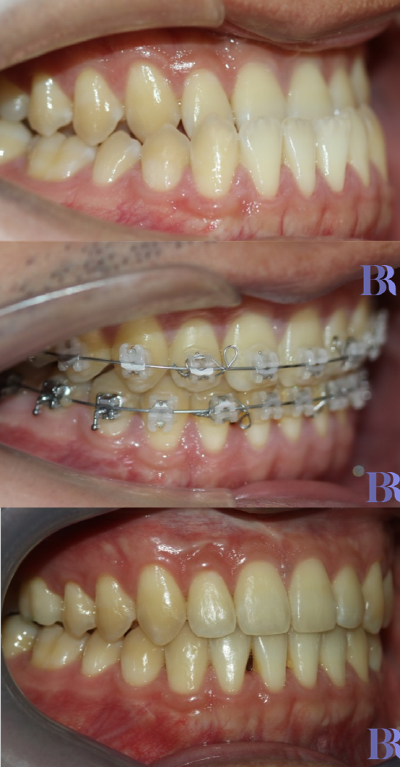

초진 입안사진입니다

치아가 거꾸로 물리고 있으나

실제 골격이 나온것에 비해서는

덜 나와 보이네요.

양악수술 대상자의 전형적인

치아 상태를 볼수 있습니다.

치성보상작용으로 인해

실제 골격에 비해 치아 간격이

좁아 보입니다

아랫니와 윗니 앞뒤 차이가

외모에 비해 심하지는 않습니다

치료 종료 후 입안을

촬영한 사진입니다

심미적일 뿐만 아니라

초진 시 보다 훨씬 더

건강해 보이지 않나요?

초진->수술직후->치료종료후

초진->수술직후->치료완료후

구내사진입니다.

정말 치료가 잘되었죠?

양악수술 전후 변화를

한눈에 보실 수 있습니다.